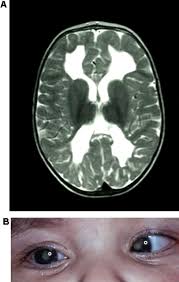

Purpura fulminans is an acute, often fatal, thrombotic disorder which manifests as blood spots, bruising and discolouration of the skin resulting from coagulation in small blood vessels within the skin and rapidly leads to skin necrosis and disseminated intravascular coagulation.

Purpura fulminans (pf) is a rare, potentially fatal complication of disseminated intravascular coagulation that is commonly associated with severe bacterial infections such as those caused by the bacterium neisseria meningitidis purpura fulminans. Early recognition and prompt treatment is essential to reduce morbidity and mortality.